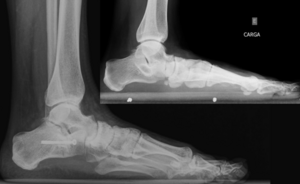

Для диагностики плоскостопия используют данные рентгенографии с рентгенометрией и плантографии при отпечатке подошвы стопы. По выраженности проявлений выделяют три степени продольного и четыре степени поперечного плоскостопия; продольное плоскостопие может сочетаться с любой степенью поперечного плоскостопия. Предварительный диагноз «плоскостопие» может быть выставлен ортопедом на основании физикального осмотра или анализа изображений, полученных при помощи подоскопа или плантографа. Определяются правильность расположения анатомических ориентиров стопы и голеностопного сустава, объём движений и углы отклонения стопы, реакция сводов и мышц на нагрузку, особенности походки, особенности износа обуви[4][2][3].

Другим методом диагностики продольного плоскостопия является измерение расстояния между бугристостью ладьевидной кости (костный выступ, находящийся ниже и спереди от медиальной лодыжки) и поверхностью опоры. Измерение проводят обычной сантиметровой линейкой в положении осматриваемого лица стоя. У взрослых мужчин это расстояние должно быть не менее четырёх сантиметров, у взрослых женщин не менее трёх сантиметров. Если соответствующие цифры ниже указанных границ, констатируется понижение продольного свода. Диагностика плоскостопия включает также анализ внешнего вида обуви пациента — при продольном плоскостопии происходит снашивание внутреннего края каблука и подошвы. Типичным проявлением симптоматического продольного плоскостопия является боль, зависящая от нагрузки, с возможной локализацией в средней части или во всей стопе. Продольное плоскостопие отрицательно влияет на всю биомеханику нижних конечностей, приводя к перегрузке медиальной группы мышц бедра, стабилизирующих голень, что проявляется энтезопатией «гусиной лапки» и в ряде случаев симптомами, сходными с клиническими проявлениями остеоартроза коленного сустава. Причиной типичных для продольного плоскостопия, но односторонних изменений, чаще всего является разница в длине ног (симптомы возникают на стороне более длинной ноги). Поперечное плоскостопие проявляется характерным внешним видом, а именно исчезновением поперечного свода и некоторыми другими объективными признаками[4][1].

Так же как и продольное плоскостопие, поперечное плоскостопие может длительно быть бессимптомным. Однако со временем возникают характерные изменения внешнего вида поперечного свода в дистальной части стопы, где свод исчезает, вместо него формируется «валик», жалобы на боли в области головок плюсневых костей при нагрузке, обычно сопровождающиеся появлением в этих зонах участков гиперкератоза. Последние хорошо определяются при пальпации этой области. Вторым типичным проявлением поперечного плоскостопия является изменение формы пальцев стоп, известное как «молоткообразная деформация». Причиной этого является ретракция сухожилий сгибателей пальцев в результате их хронической травматизации. Возникают сначала нефиксированные, а затем стойкие сгибательные контрактуры в проксимальных и дистальных межфаланговых суставах, разгибательные контрактуры в плюснефаланговых суставах. В начальных стадиях эти деформации малозаметны, в выраженном виде они вызывают серьёзные проблемы, связанные с травматизацией наиболее выступающей части пальцев обувью. Одной из частых деформаций, сопутствующих поперечному плоскостопию, является Нallux valgus, который обычно формируется вследствие варусного отклонения первой плюсневой кости и вальгусной деформации в первом плюснефаланговом суставе. При этом угол между осью первого пальца и первой плюсневой костью превышает пятнадцать градусов. Хотя причины данной деформация могут быть различными, наиболее часто её прогрессирующий вариант наблюдается у лиц с декомпенсированным поперечным или комбинированным плоскостопием[4][1].